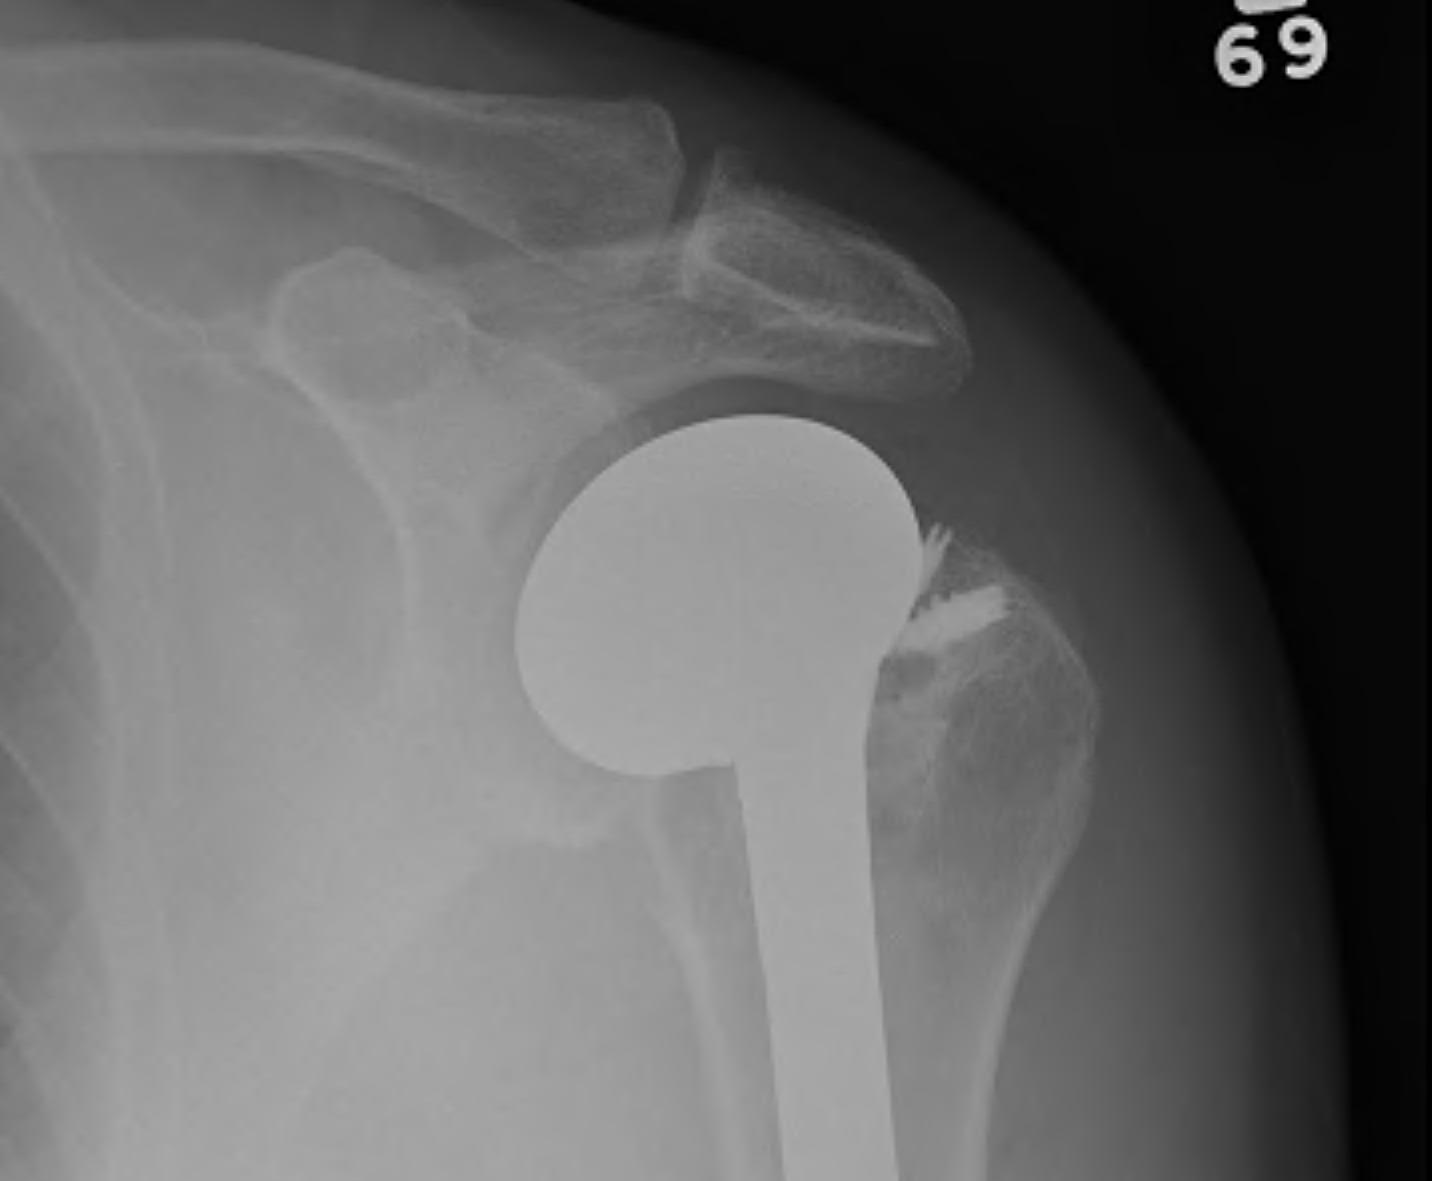

Repaired rotator cuff

MRI demonstrating intact cuff